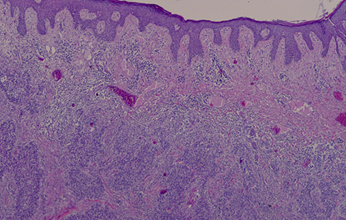

Se intervino en mayo del 2021 realizando exéresis del implante de 4x2,5 cm con márgenes libres. La anatomía patológica confirmó el hecho de ser una metástasis y no un primario ya que no había afectación de epidermis, el tumor crecía desde las capas inferiores a las superiores.

Fig. 1. Metástasis cutánea de carcinoma anal

Fig.3. Imagen histológica.